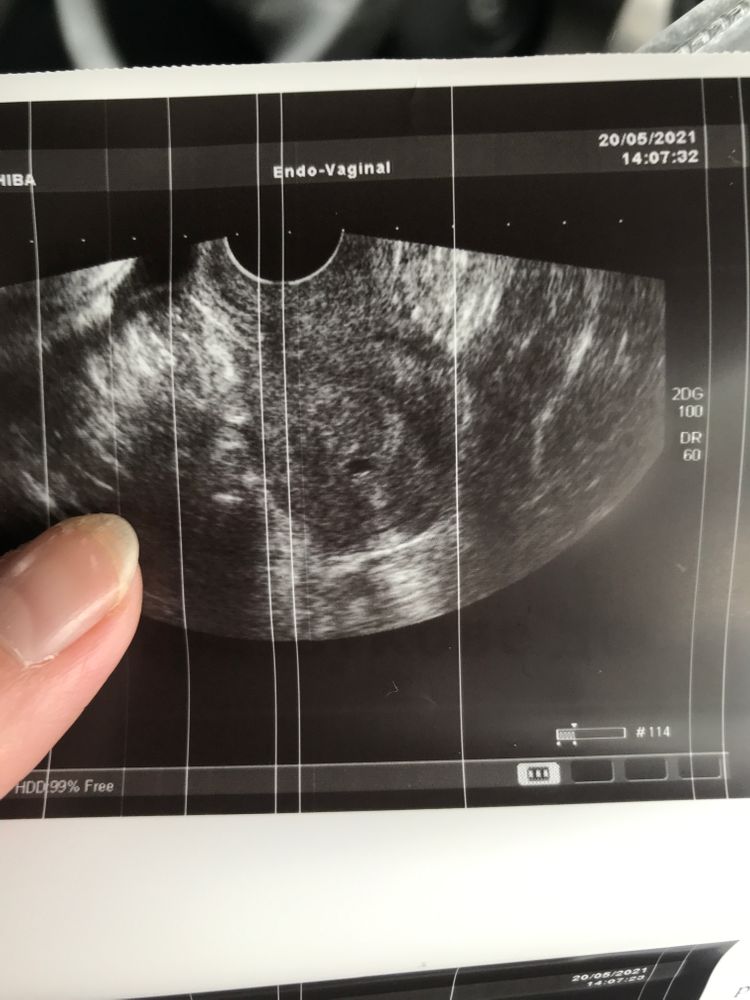

На узи плодное яйцо - как врач говорит

Yana, была на ещё одном узи , это образование присутствует

Аденомиоз мне кажется не может быть одной точечной локализации, мне ставили такой диагноз по УЗИ, но делали на 3Д и там как то эти участки закрашивались и было понятно

Повторите через неделю но сделайте на хорошем аппарате чтобы точно, ПЯ при отрицательном ХГЧ в крови я думаю не бывает